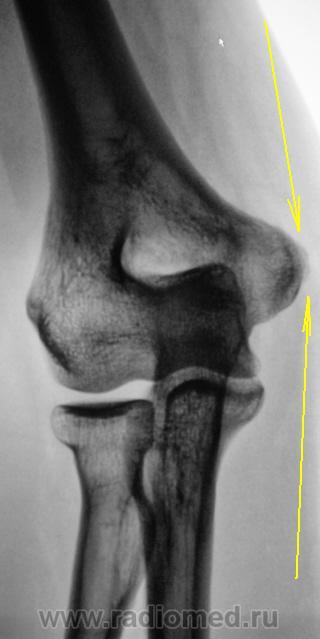

Пациентка в течение года предъявляет жалобы по поводу болей в локтевом суставе. Произведено полное клинико-лабораторное обследование. Увы, ничего не найдено. Пациентка направлена на рентгенографию локтевого сустава с единственной целью - "консультация в области".

Похоже на эпикондилит, он же - "теннисный локоть". Сначала - физиолечение+инъекции стероидов в надмыщелок, при неэффективности - оперативное лечение.